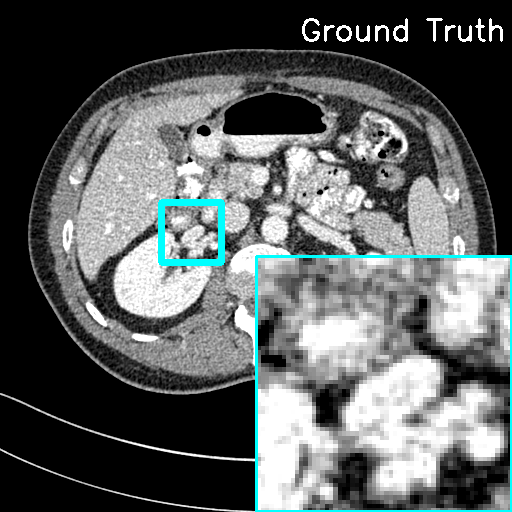

(ii) Domain-shift cases. In this study, Clinical LDCT dataset is selected as the testing set, while the AAPM Mayo Clinic dataset still remains as the training set for our model. Although the imaging operators of the training and testing sets remain the same, the CT images originate from different scanners. For comparison, we applied the traditional FBP algorithm directly to the Clinical LDCT dataset to obtain the reconstruction results. Fig. 10 shows the representative reconstructions with lesions using different methods. It can be seen that the proposed F-LInFBP and L-LInFBP methods achieve higher fidelity reconstructions with clear tissue depiction, i.e., better preserving lesion details. Moreover, subjective assessments from experienced radiologists are also conduced to evaluate the potential clinical application. Table 6 lists the average scores, indicating the potential application of the proposed LInFBP in clinical settings. These results highlight the reliability of the proposed LInFBP against variations in imaging operators and domain shifts.